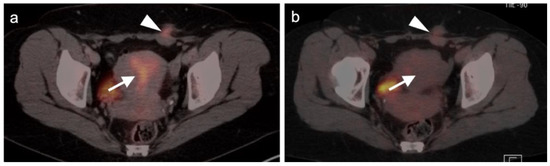

3.1. Prostate Cancer

3.2. Urothelial Carcinoma